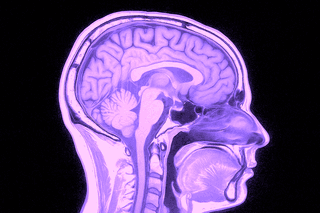

Undersökningen ger högupplösta tvärsnittsbilder av hjärnans vävnad, ventrikelsystem, kärl och kranialnerver. MR används både vid akuta insjuknanden (t.ex. stroke eller plötslig medvetandepåverkan) och vid planerad utredning av mer långvariga eller diffusa symtom. Den är även värdefull för uppföljning av tidigare fynd såsom cystor, aneurysm eller tumörer, samt vid misstanke om neurodegenerativa sjukdomar som multipel skleros, Parkinsons sjukdom eller olika former av demens.

En MR-undersökning av hjärnan tar cirka 20–30 minuter och är helt smärtfri. Du ligger stilla i en magnetkamera som tar tvärsnittsbilder av hjärnans strukturer. Undersökningen sker utan remiss från vårdcentral – vi utfärdar den direkt i samband med din bokning. Resultatet granskas av specialistläkare i neuroradiologi och du får ett skriftligt utlåtande inom några dagar.